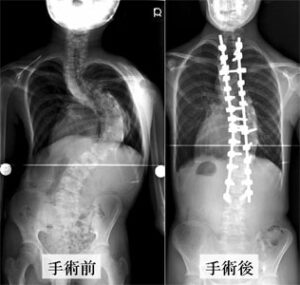

手術方法はどのようなものになりますか?

側弯の種類、弯曲によっても異なりますが、前方からと後方からの2種類のアプローチ方法があります。

前方法は肋骨を切ったり、おなかを切ったりして脊椎に到達する方法です。

後方法は背中をまっすぐに切って、脊椎に到達する方法です。一般的に胸椎のカーブは後方より手術するケースが多いようです。

スクリューを設置して矯正したり、またフック、あるいはワイヤーを用いて脊椎を矯正します。

使う金属の素材はチタンやステンレス製です。矯正した後は、骨盤から採取した自分の骨を移植して、その位置で骨をくっつけます。

肋骨の出っ張りが著しい場合は、肋骨を何本か切除することがあります。